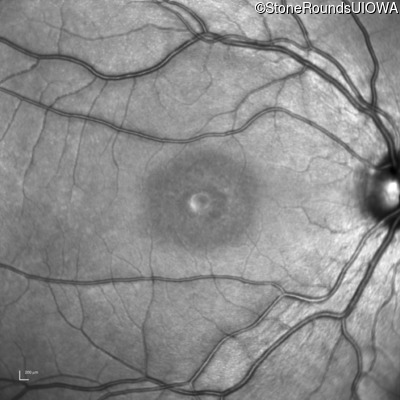

AR Stargardt Disease (IIA)

Age at visit:

14 years

OD

OS

20/32

20/20 -2

AR Stargardt Disease

ABCA4

Gly607Arg GGG>AGG

Gly1961Glu GGA>GAA

AR